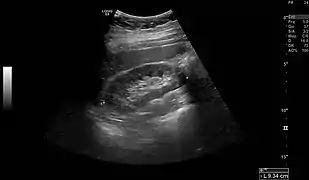

Normal adult right kidney as seen on abdominal ultrasound with a pole to pole measurement of 9.34 cm.